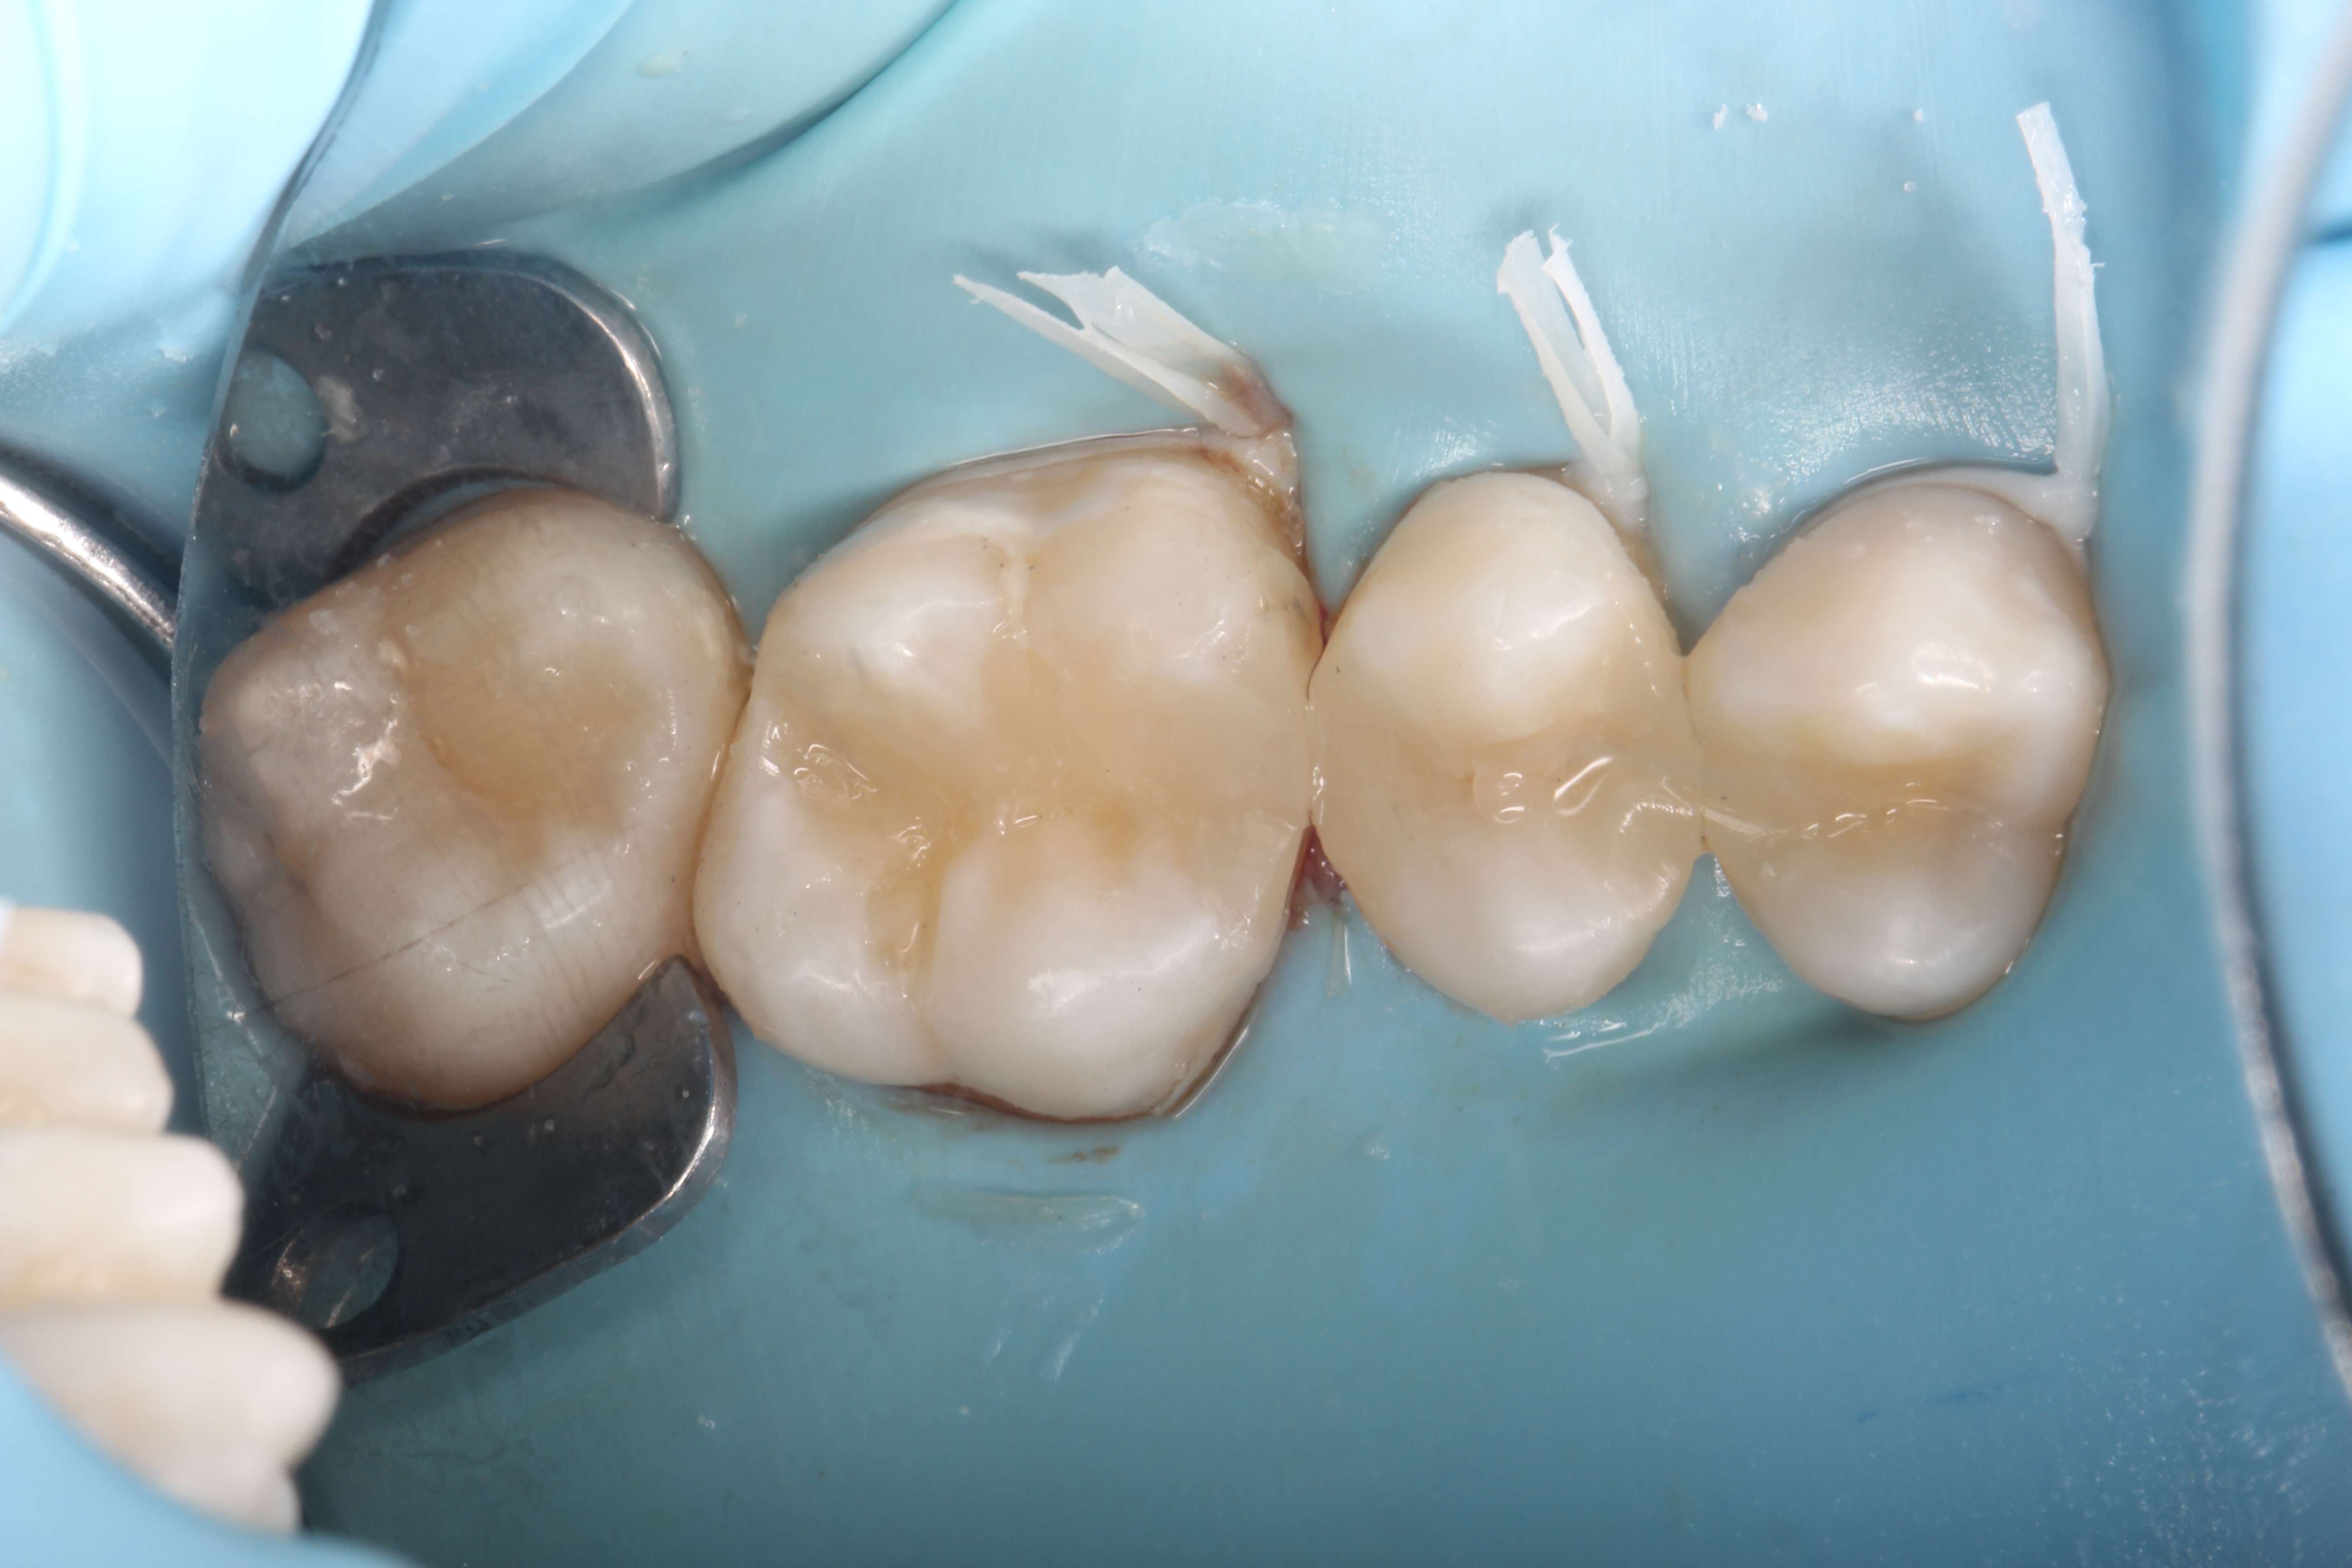

Crowns and onlays by Professor Brian Millar

This course solidified my knowledge and allowed me to practice various cuspal coverage treatments including overlays, onlays and vonlays. I was able to learn about the different preparation techniques and margins required for each indirect material.